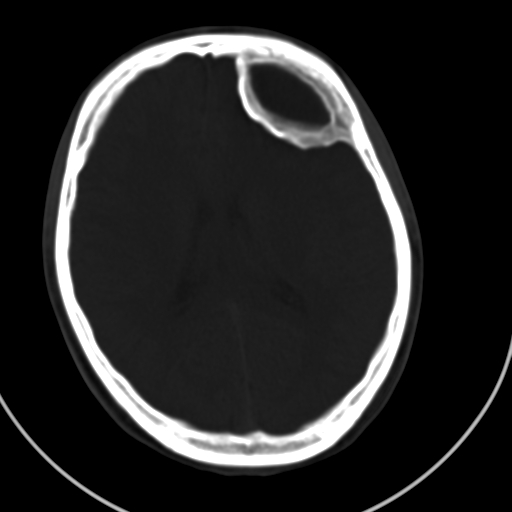

标题: CT21939:男20岁,外伤一年后,现头疼. [打印本页]

标题: CT21939:男20岁,外伤一年后,现头疼.

硬膜外血肿机化

硬膜外血肿伴包膜钙化

左侧额部硬膜外血肿机化、骨化。

左侧额部硬膜外血肿机化、骨化